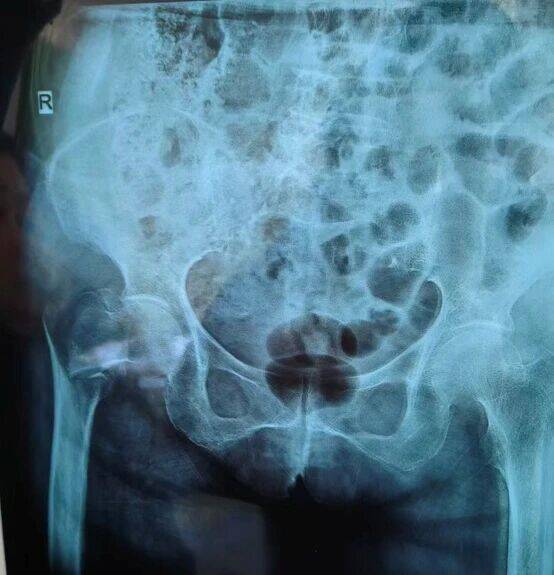

今年90岁的王奶奶(化名),因在家中不慎摔倒,导致右侧髋部剧烈疼痛、无法活动,被紧急送至中心。经检查,确诊为“右侧股骨粗隆间骨折”。对于年轻人而言,这样的骨折可通过手术获得良好恢复,但对于已届鲐背之年的王奶奶来说,却是一次生死考验。

在麻醉科金延武主任团队的精准护航下,采用了神经阻滞麻醉方式,全程严密监测王奶奶的生命体征。骨科高红伟主任团队凭借丰富的经验,选择了创伤小、出血少、固定可靠的微创手术方案。术中在C型臂透视下牵引复位骨折,通过几个3-5cm切口,轻柔、迅速、精准地置入大小合适的股骨髓内钉,力求将手术创伤降至最低。整个手术过程如行云流水,仅用一小时便顺利完成,出血量被控制在了极低水平。